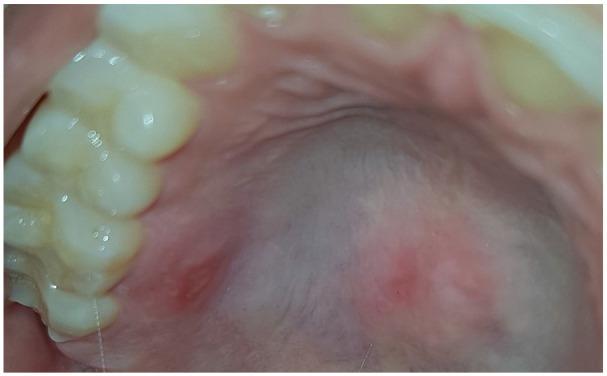

Thermal burns of the oral cavity usually arise from ingestion of hot foods or beverages. A 38-year-old female patient presented with two painful ulcerative erythematous patches of the palate. The patient was consulted on the same day lesions appeared. Medical history was unremarkable. Clinically significant self-inflicted injuries may result in wide ulcers in the mouth and usually do not take less than 2 weeks to heal, whereas our patient, treated with low-level laser therapy, had a complete response in day 4, after 2 days of treatment. The fact that multiple lesions were present signaled against the World Health Organization exclusion diagnosis of erythroplakia for red patches. A traumatic ulcer, regardless of its cause of origin, usually heals within 2 weeks, after the source of injury is resolved. A thermal burn in the oral cavity usually takes longer than that to heal, but whenever this time frame is not respected, the suspicion of a potentially malignant disorder should always arise, and a biopsy should be performed. The present case showed two painful thermal burns with great results in terms of speeding up the relieve of symptoms and healing time with soft laser as opposed to the traditional treatment with oral topical corticosteroid.

口腔热烧伤通常由摄入过热的食物或饮料引起。一名38岁女性患者腭部出现两处疼痛性溃疡性红斑。病变出现当天患者前来就诊。病史无异常。具有临床意义的自残伤可能导致口腔内出现广泛溃疡,通常愈合时间不少于2周,而我们的患者接受低强度激光治疗后,治疗2天后在第4天完全康复。存在多个病变这一事实排除了世界卫生组织对红斑性增殖性红斑的排除诊断。创伤性溃疡无论其起源原因如何,在损伤源消除后通常在2周内愈合。口腔热烧伤通常愈合时间更长,但只要不符合这个时间框架,就应始终怀疑可能存在恶性疾病,并应进行活检。本病例显示两处疼痛性热烧伤,与口服局部用皮质类固醇的传统治疗相比,软激光在加速症状缓解和愈合时间方面效果显著。